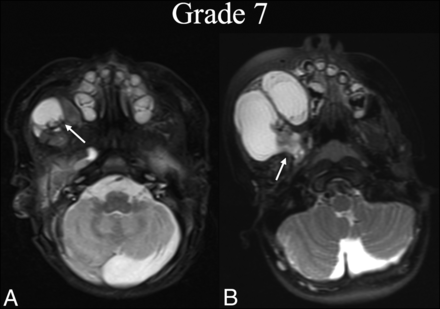

BDL grade 7 progression. A neonate boy with right facial prominence was found to have a de Serres stage II macrocystic LM. A, Initial T2 fat-suppressed axial MR imaging at the level of the hard palate shows involvement of the right buccal space (white arrow). B, Three years later, before any intervention, T2 fat-suppressed axial MR imaging at the same level shows BDL grade 7 progression with clear volume increase and extension into the masticator and parapharyngeal (white arrow).